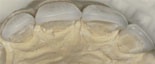

Fyra keramiska skalfasader före och efter behandling - sett från sidan.